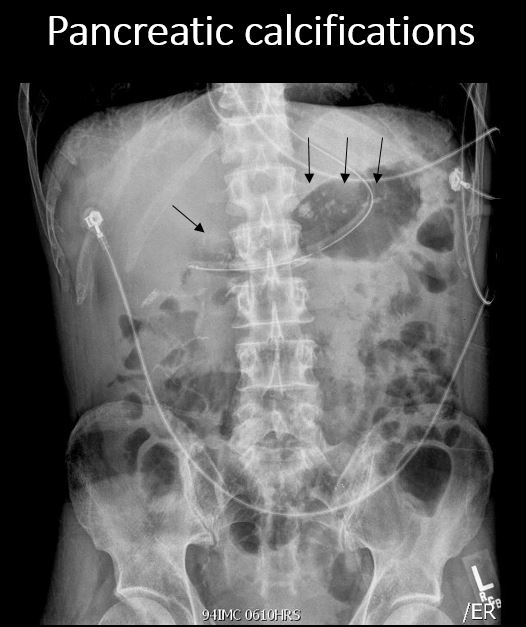

There are calcifications in the pancreas. [Yes/No]